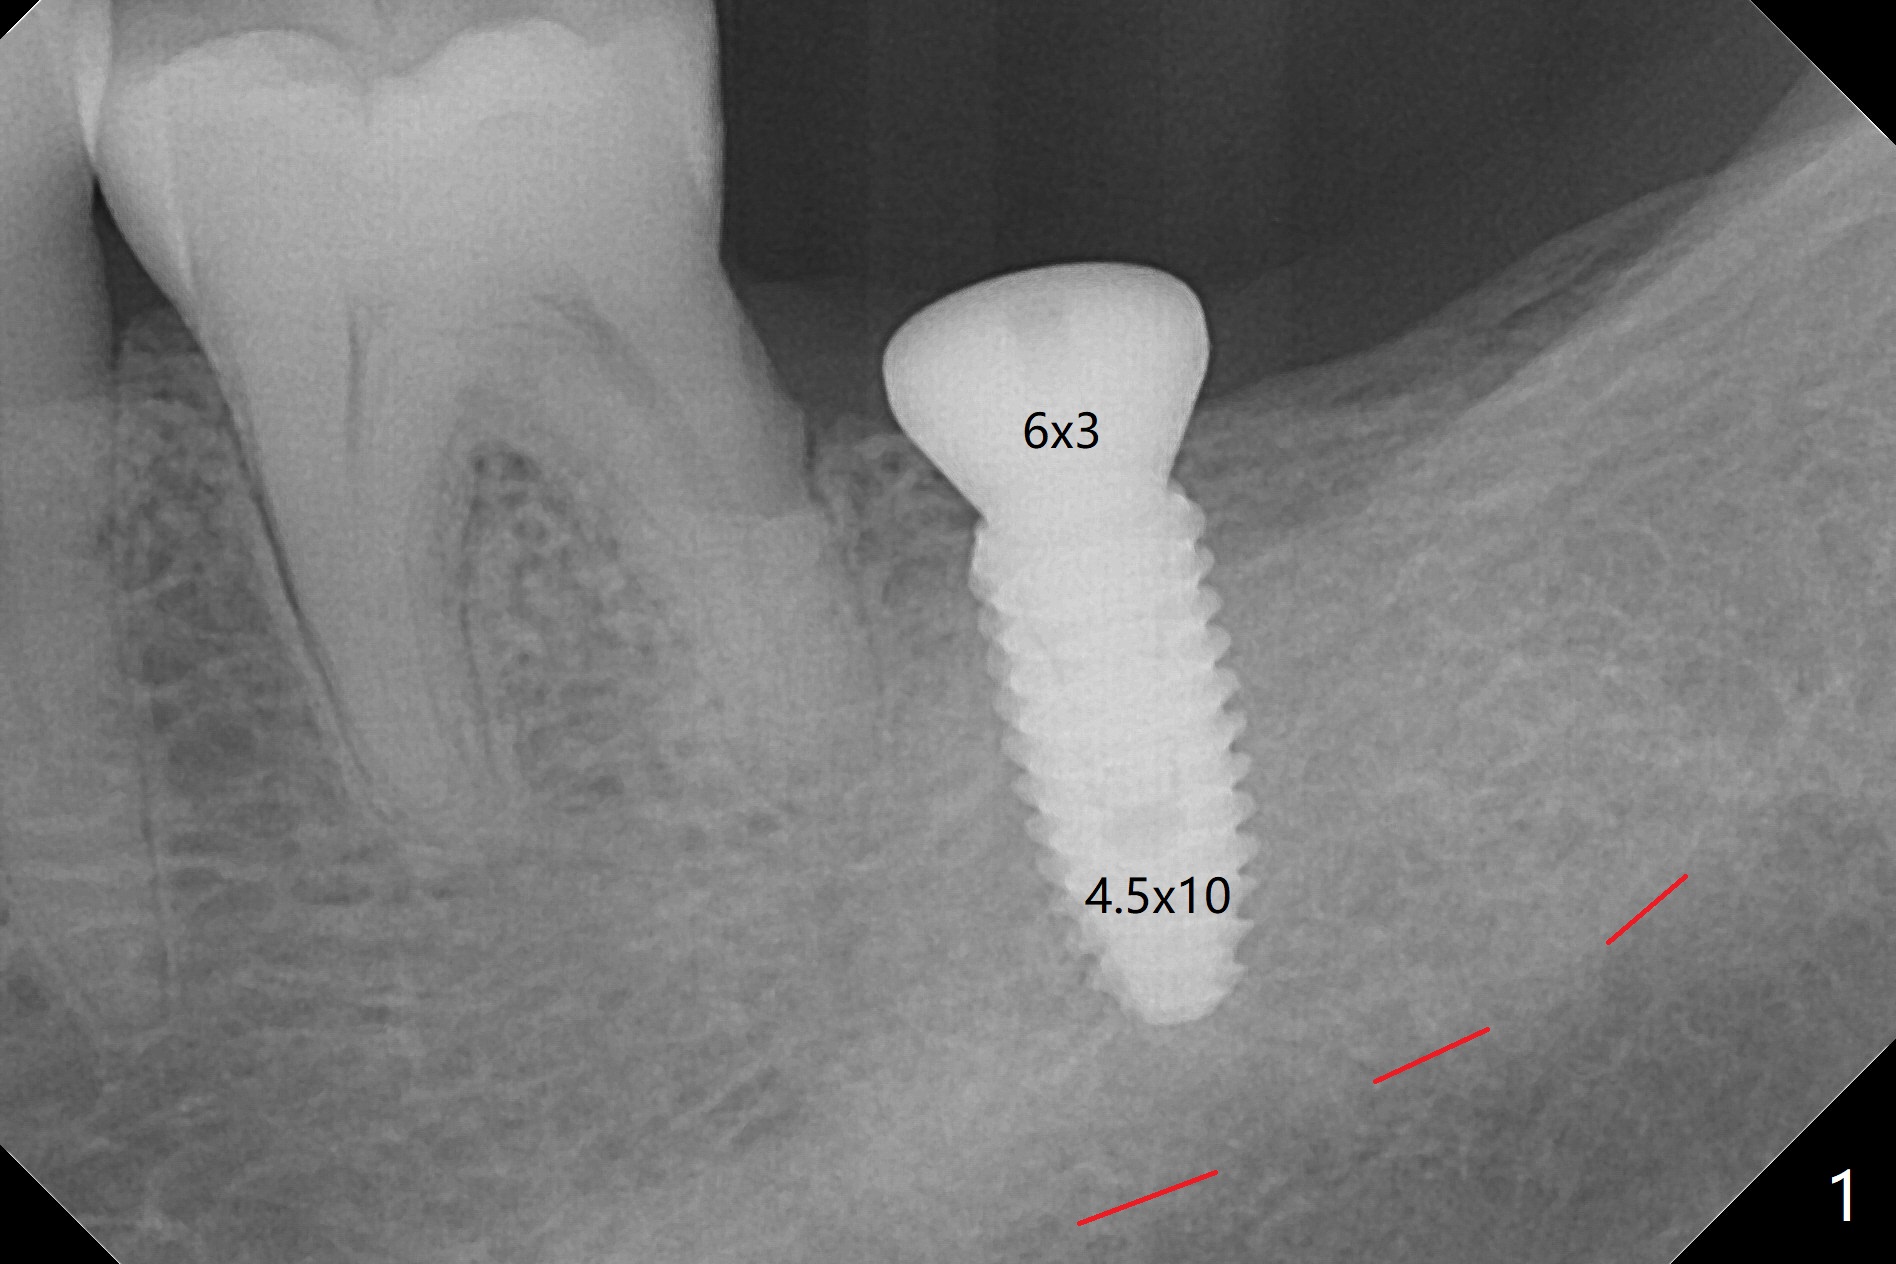

After osteotomy is finished as planned at #18, the guide is removed.  The mesial wall of the osteotomy seems to be normal (hemorrhage).  There is no sign of residual roots.  A 4.5x10 mm implant is placed with stability.  Periodontal probe is used to confirm the implant being slightly subcrestal.  A 6x3 mm healing abutment is placed (Fig.1 (red dashed line: the superior border of the Inferior Alveolar Canal)).  The patient is satisfied with speed and comfort of the procedure as compared to his previous ones (#2,31, and 15).  There is no postop discomfort.